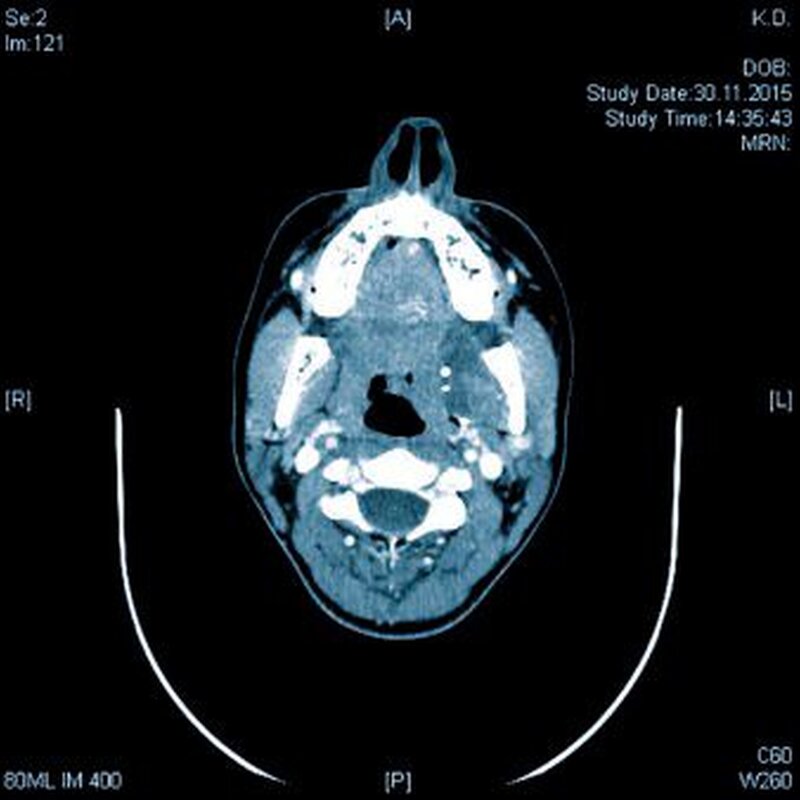

Zur genauen räumlichen Zuordnung der Verschattungen unterhalb der Incisurae semilunares wurde eine dentale digitale volumentomografische Untersuchung durchgeführt (Abbildungen 2 bis 4).

Für die Darstellung von Lymphknoten oder Speichelsteinen stellt die Sonografie die Methode der Wahl dar. In der Regel ist keine Abgrenzung zu weichgeweblichen Strukturen möglich. Dies muss bei kalzifizierenden Metastasen oder hartgewebebildenden Neoplasien (wie Osteosarkome) berücksichtigt werden. Um eine eindeutige Zuordnung zu den umgebenden Weichgewebe-strukturen gewährleisten zu können, sollte eine 3-D-Summationsaufnahme (DVT, CT) durchgeführt werden.